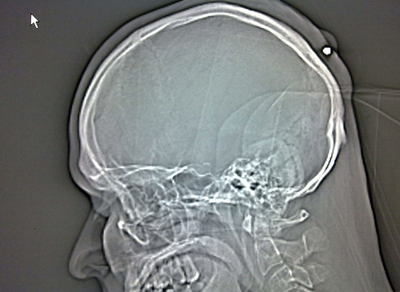

ニュース 社会 頭にナイフ刺さった男性、サンパウロで保護 2014年1月8日 16:40 発信地:バウル/ブラジル [ 中南米 ブラジル ] このニュースをシェア ‹ › ❮ 1/3 ❯ ブラジル、サンパウロ(Sao Paulo)の北350キロほどにあるバウル(Bauru)の病院で、頭にナイフが刺さったままの男性(写真右)と、頭部のX線写真(写真左、2014年1月7日提供)。(c)AFP/Military Police of the state of Sao Paulo 画像作成中 ! 【1月8日 AFP】ブラジル・サンパウロ(Sao Paulo)州の憲兵隊は7日、頭にナイフが刺さったままの男性の写真および頭部のX線写真を公開した。男性は保護され、サンパウロの北方約350キロのバウル(Bauru)の病院で治療を受けている。警察当局は事件とみて捜査を進めているという。(c)AFP 社会 一覧へ> メディア・報道関係・法人の方向け 写真・動画 購入のお問合せ>